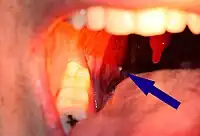

| A tonsillolith lodged in the tonsillar crypt | |

A tonsillolith protrudes from the tonsil